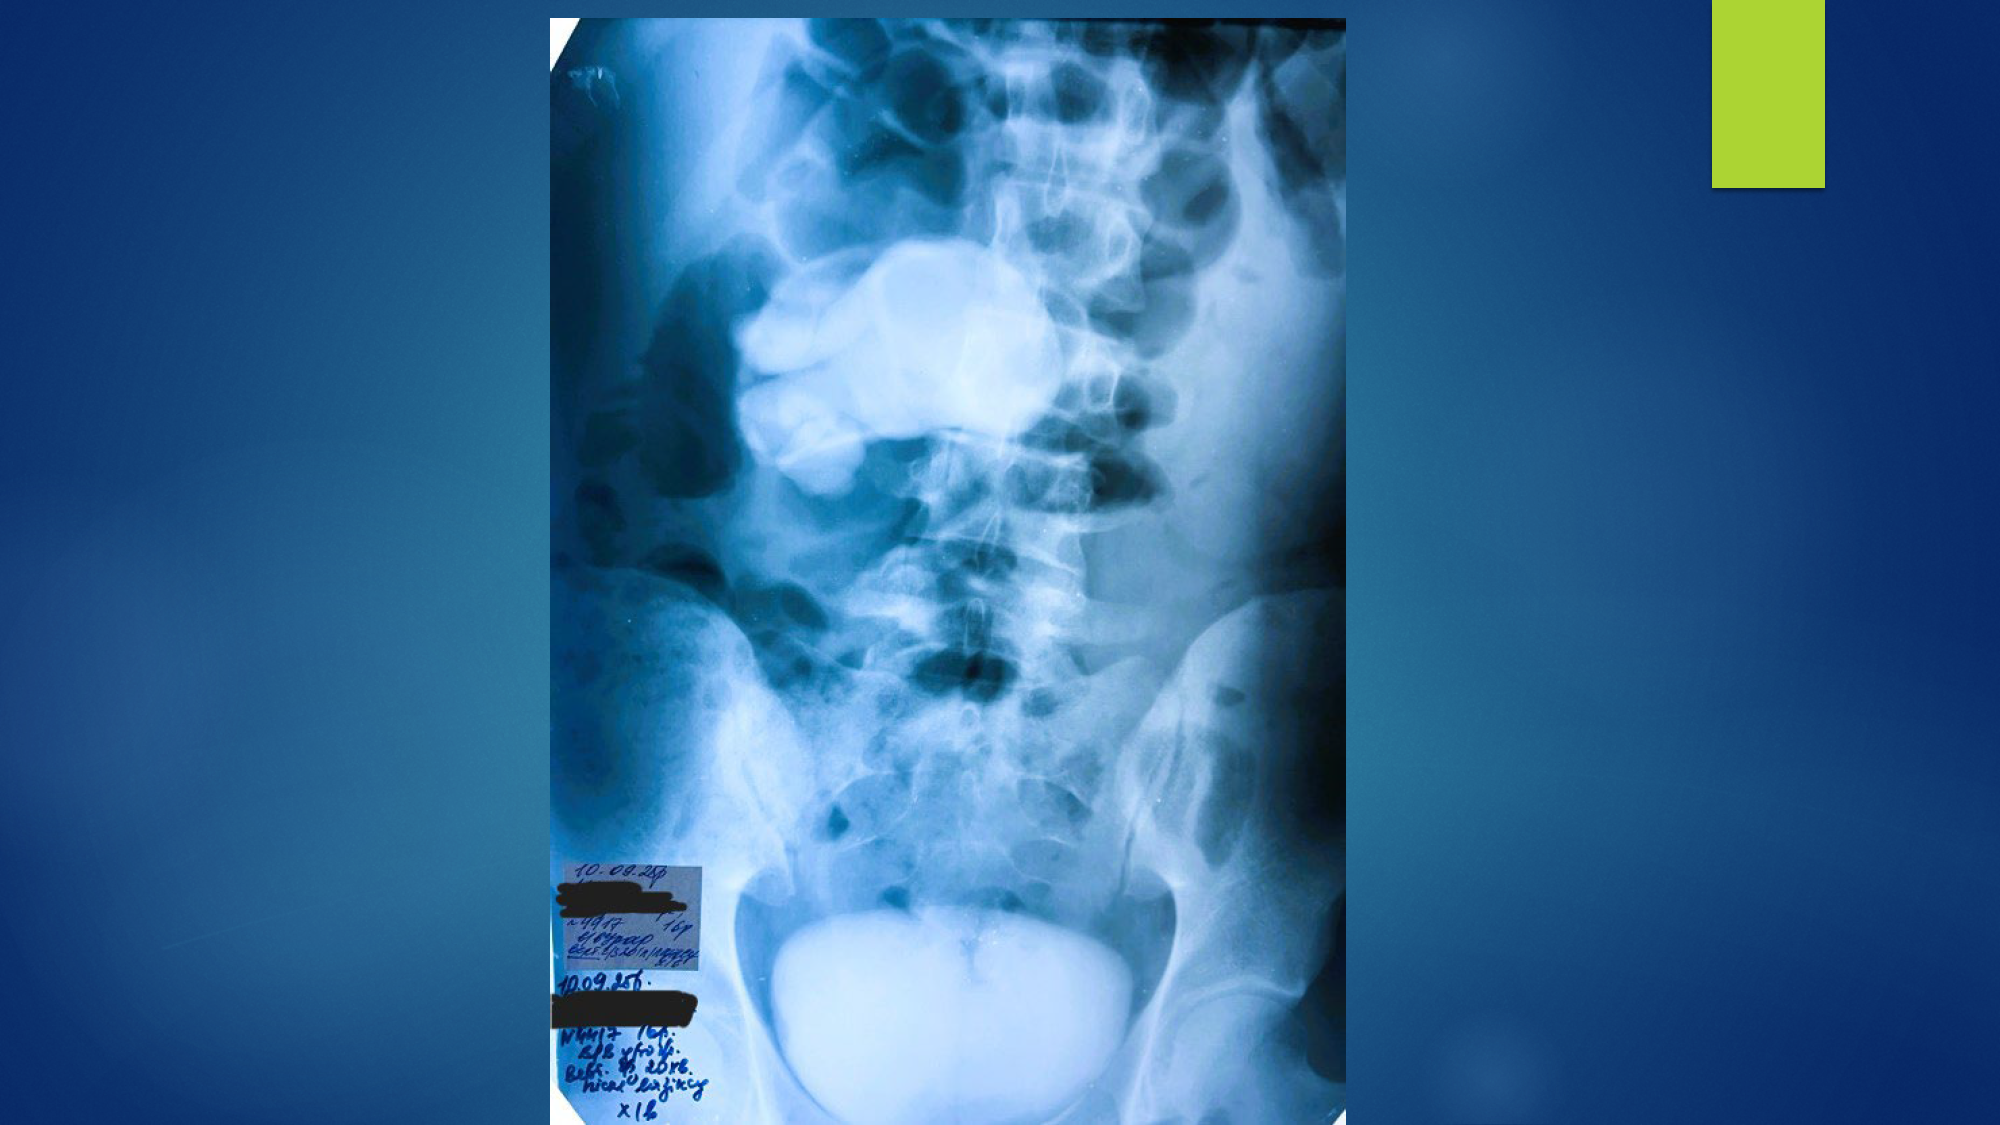

Хлопчик Д.,15 років, гідронефроз 3 стадії зліва